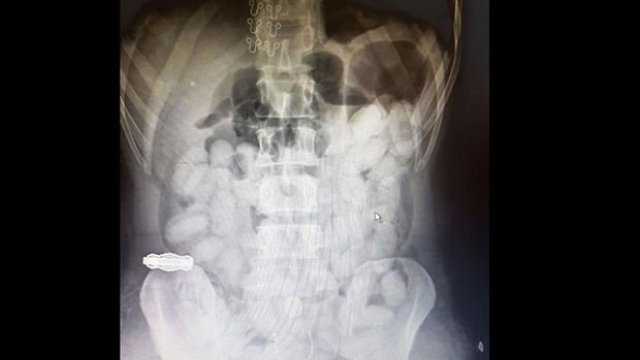

DHA'nın haberine göre, Antalya İl Emniyet Müdürlüğü Narkotik Suçlarla Mücadele Şube Müdürlüğü ekipleri, 18 Ekim 2017 tarihinde, Brezilya'nın Sao Paulo kentinden İsviçre'nin Zürih şehri aktarmalı Antalya seferini yapan uçakla Türkiye'ye gelen Washington Lincoln Arves Tolentino'nun uyuşturucu kuryeliği yaptığı istihbaratı üzerine operasyon düzenledi. Antalya Havalimanı'nda önlem alan ekipler, uçaktan inen şüpheliyi gözaltına aldı. Mahkemeden alınan kararla hastanede yapılan iç muayenesinde, Tolentino'nun mide ve bağırsak kısmında, kokain içerdiği değerlendirilen kapsül şeklinde, çok sayıda cisim olduğu tespit edildi. Hastanede gözetim altında tutulan Tolentino'nun midesinde, 59 kapsül içinde, 649 gram kokain doğal yollarla çıkarıldı. Hastanedeki tedavisinden sonra emniyete götürülen Brezilyalı Tolentino, çıkarıldığı mahkemece tutuklandı.